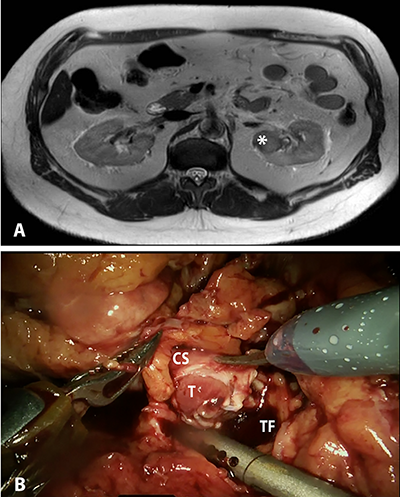

On gross pathologic analysis, a yellow-tan, circumscribed and lobulated mass measuring 4.2 x 3.5 x 2.7 cm was found in the cortico-medullary junction of the upper pole.  A pale tan tumor thrombus was identified in the renal pelvis, while no thrombus was identified in the renal vein.  On microscopic examination, focal necrosis and multiple foci of osseous metaplasia were noted (Figure 2).  On immunohistochemistry, tumor cells were positive for PAX8, focally positive for CA-IX, and largely negative for CK903, p63, and GATA3.  These findings are consistent with collecting duct carcinoma with sarcomatoid differentiation.  The tumor was found to be invading the renal pelvis, renal cortex and perinephric fat; the sinus fat and renal vasculature were uninvolved.  Thirty-five lymph nodes were removed, and seven were found to contain metastatic cancer.

Figure 2. High magnification photomicrograph showing highly infiltrative carcinoma with tubular structure, embedded in desmoplastic stroma.  The tumor cells have eosinophilic cytoplasm (arrowhead), the nuclei are large and pleomorphic, with prominent nucleoli (arrow) and coarse chromatin.  Also seen is evidence of ossification (*).